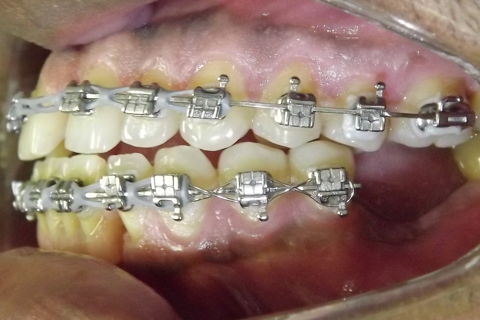

fotos iniciais do caso.

Paciente do sexo masculino, 36 anos, brauifacial. Relatava que os Diastemas lhe incomodavam muito, e em tratamento anterior o profissional fez exo de 2 incisivos centrais inferiores e instalou Prótese movel com 4 incisivos, após um tempo de uso a prótese começou a incomodar. em planejamento com o implantodontista ficou definido o fechamento dos diastemas e reabilitação dos elementos 41 e 31 com implantes.

segue as fotos do caso